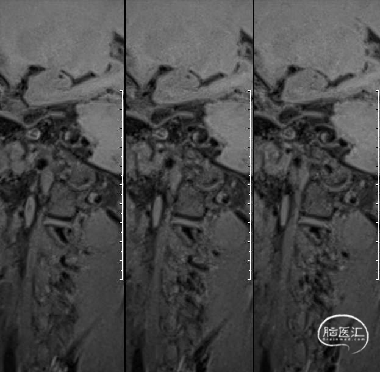

HRMRI示右侧椎动脉V4段梭形动脉瘤,瘤壁强化。

术前高分辨MRI:

HRMRI示左侧颈内动脉C3-C4段长段瘤样扩张,瘤壁明显强化。